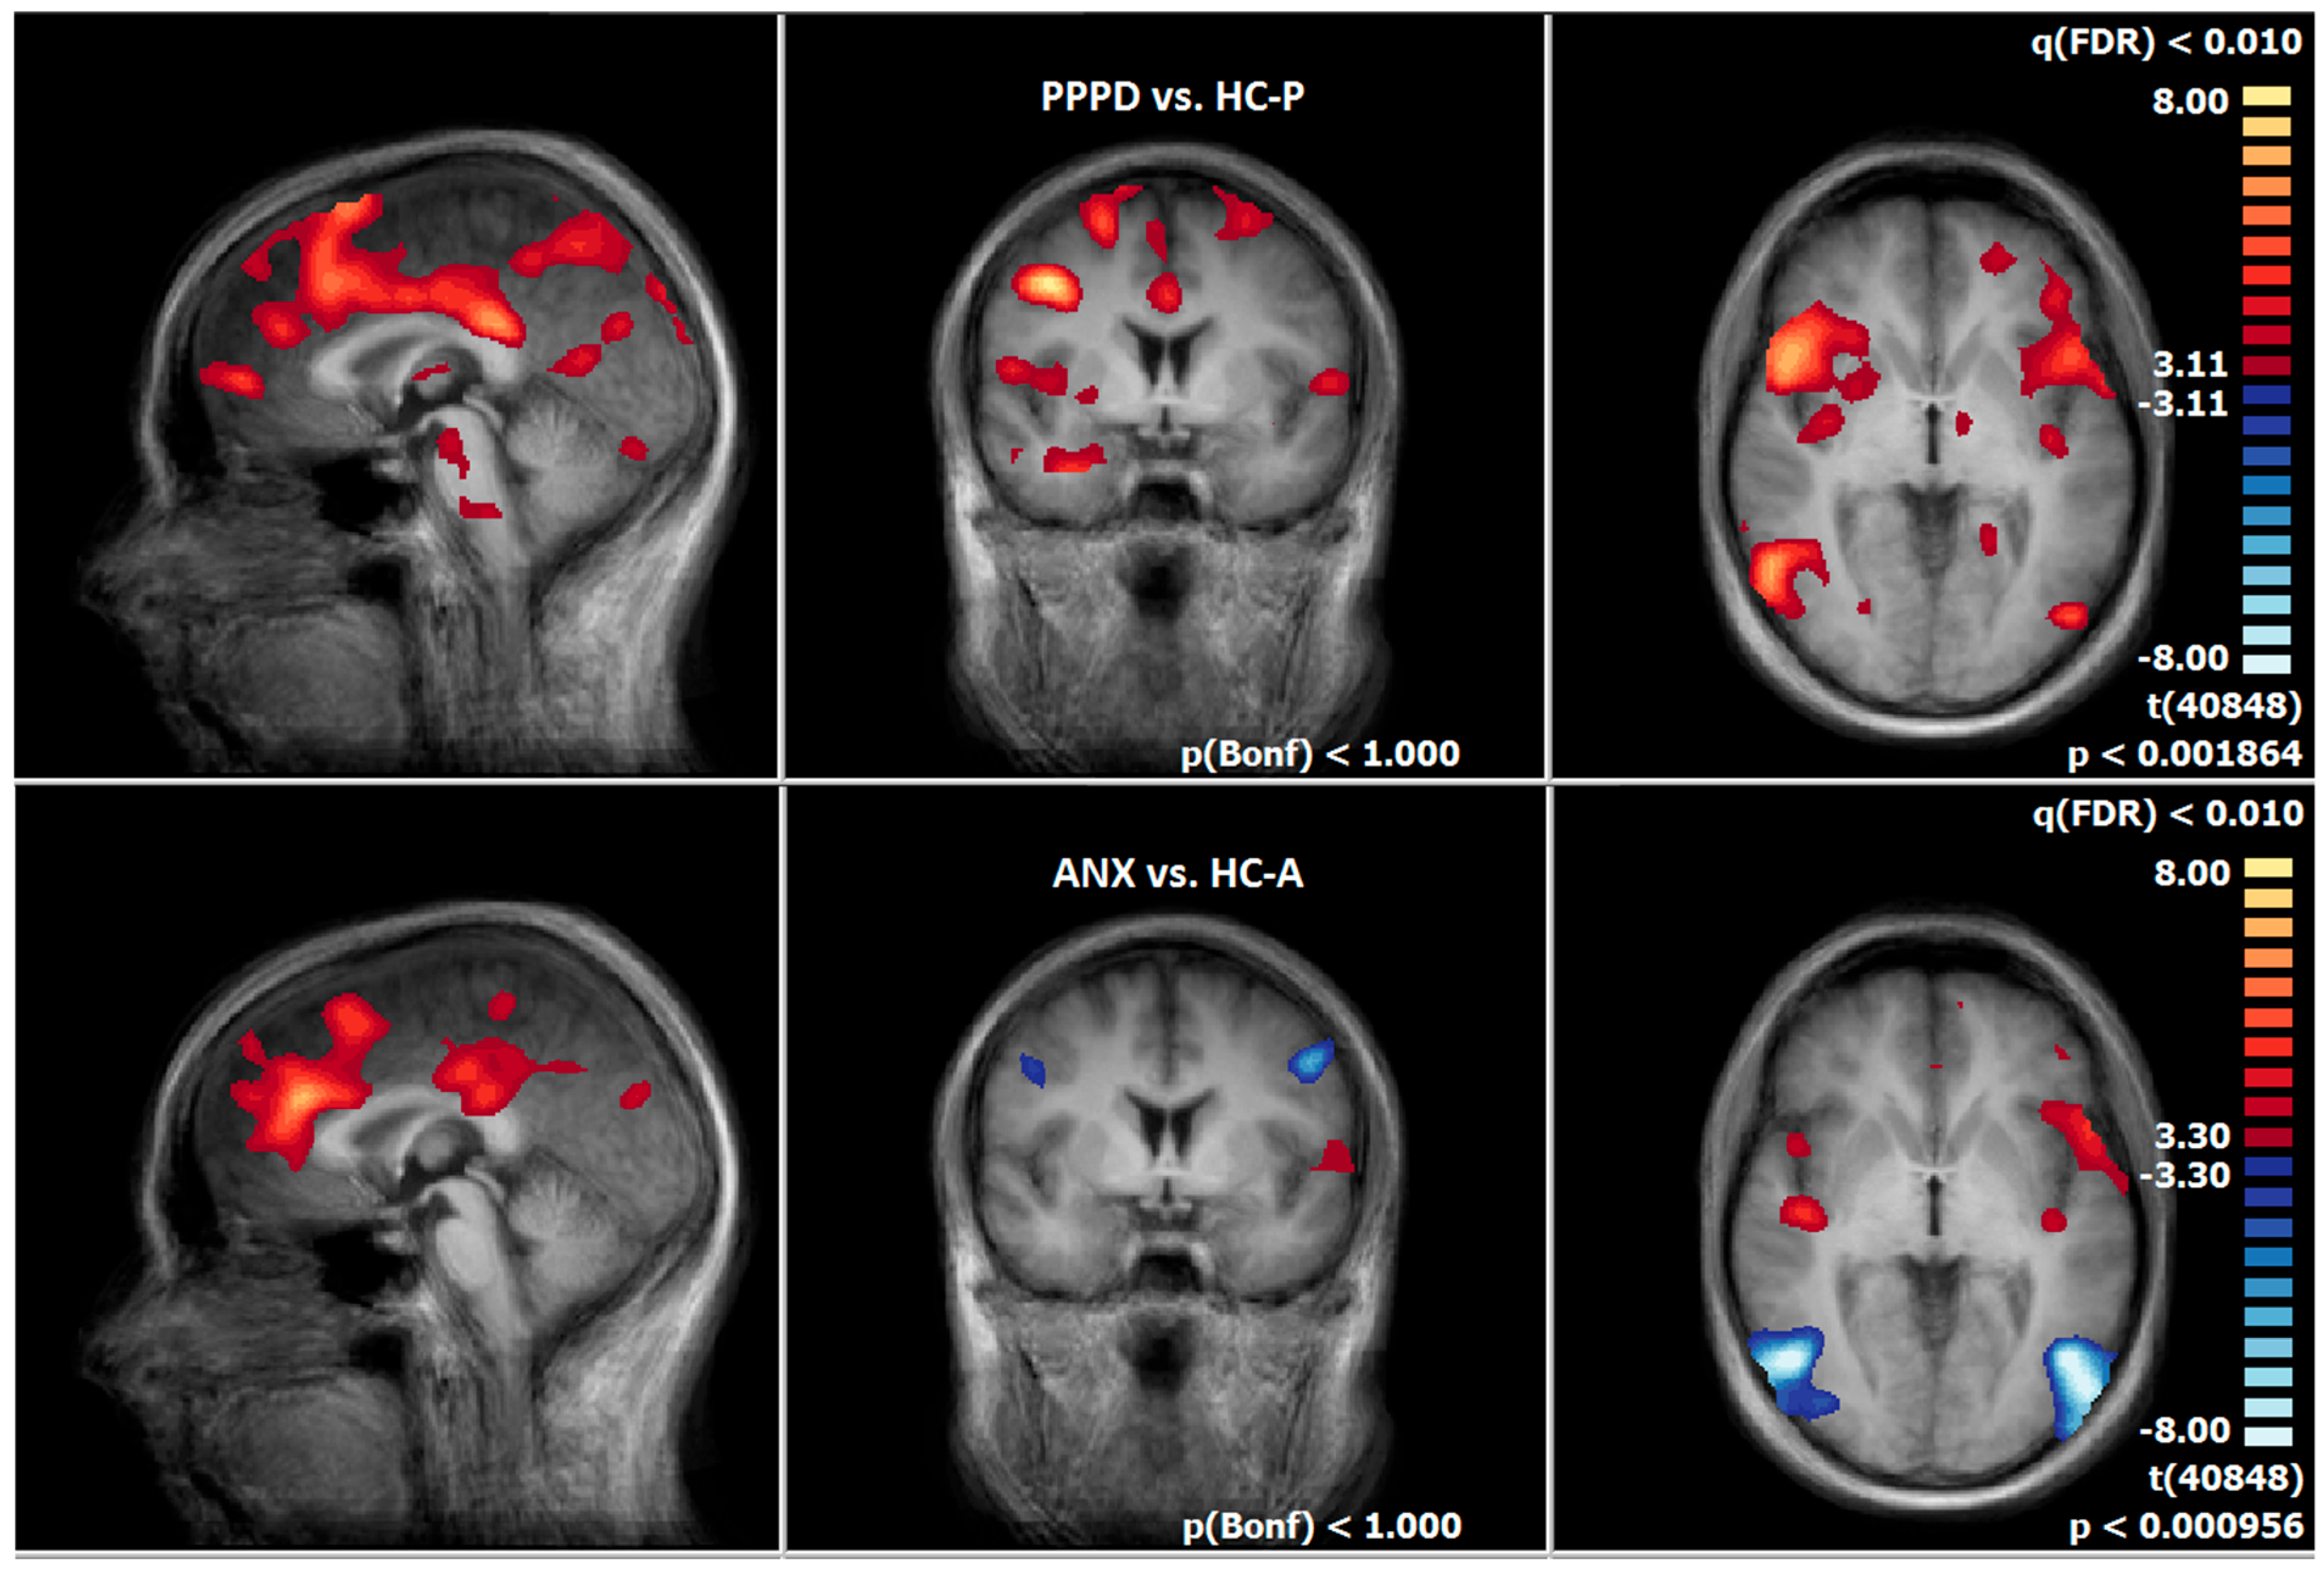

3.4. Comparison of Neuronal Responses Before and After Therapy—PPPD

3.5. Comparison of Neuronal Responses Before and After Therapy—ANX